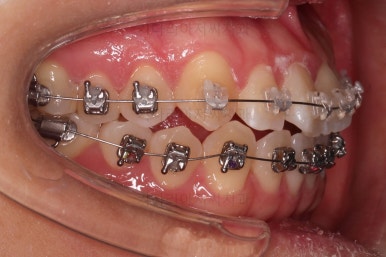

1. 처음 내원 시의 입안의 모습

부산치아교정잘하는곳 키다리아저씨치과에 처음 내원하셨을 당시의 입안 모습입니다.

얼핏 보면 많이 삐뚤어지지는 않은 편인데, 눈에 바로 띄는 앞니가 뻗쳐 있으면서 획 돌아있는데요. 정렬이 필요한 상황이었습니다.

어금니쪽은 많이 삐뚠 편은 아니었으며, 윗니 앞니가 많이 앞으로 뻗쳐 있는 상태였습니다.